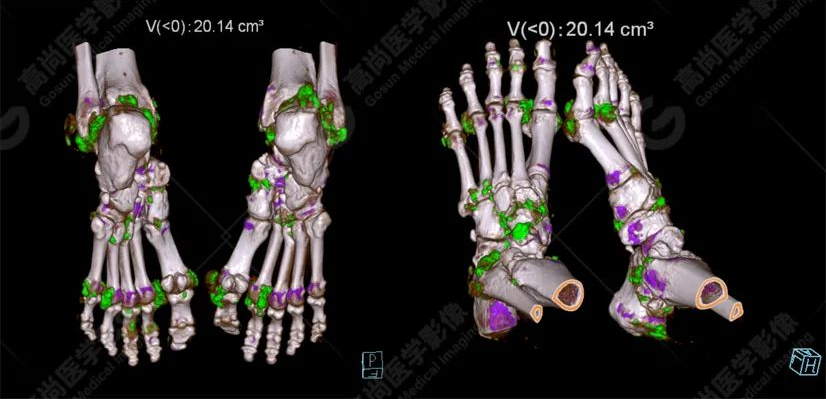

雙足VR圖像

患者為60歲男性,既往確診痛風(fēng)性關(guān)節(jié)炎,雙手及雙足多發(fā)軟組織腫塊結(jié)節(jié),疼痛不適,活動(dòng)受限,尿酸明顯增高,多次檢測(cè)尿酸超過(guò)500umol/L。